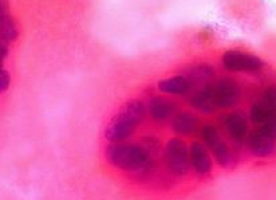

The three regimens studied have been considered low-to-moderate risk for inducing neutropenia-related complications as less than 20 percent of patients being treated with these chemotherapies experience febrile neutropenia.

The retrospective analysis included patients with breast cancer who began first-cycle chemotherapy from 2008 to 2013 using docetaxel and cyclophosphamide, also known as TC or carboplatin, docetaxel and trastuzumab, also known as TCH or doxorubicin, and cyclophosphamide, also known as conventional dose AC.